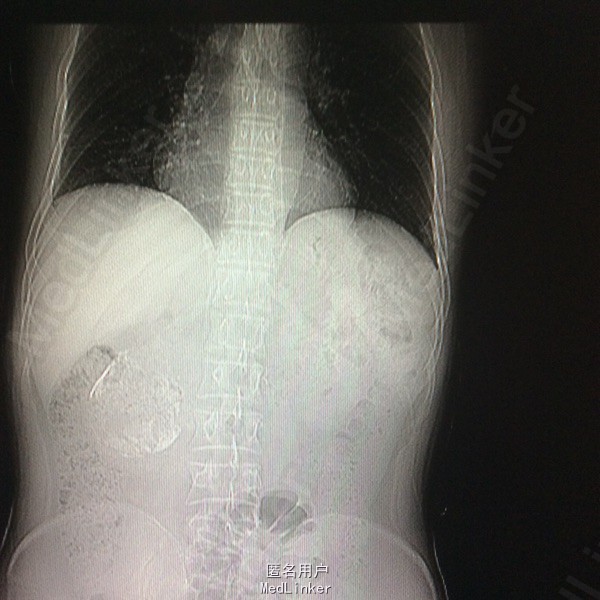

患者双下肢无明显浅感觉减退,肌力V级,肌张力不高,二便控制满意,病理征阴性。 腰椎核磁:腰1-4椎体右侧右肾下方团块状占位,大小约8#⃣6.8Cm,等T1长T2信号 腰椎Ct:占位周围见弧形钙化灶